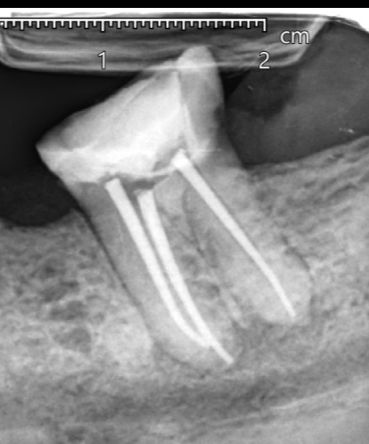

A patient complaining from severe pain in lower 7 had a previous root canal treatment, on examination tooth had severe response to percussion and root canal retreatment had to be done

🔹RC retreatment

🔹Ever x posterior